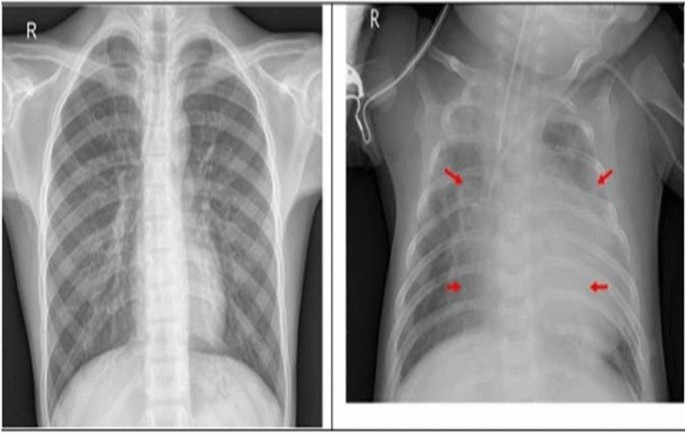

The dataset used for training and evaluation of CareAssist-GPT model includes normal cases and patients with pneumonia in chest X-ray images. This multimodal dataset guarantees that the model is trained with images of different conditions, as well as the corresponding vital signs and clinical text records. The use of both normal and pathological samples is helpful in enhancing the model’s diagnostic performance and its applicability. Figure 3 shows the Chest X-ray with and without pneumonia. Figure 3 presents a visual comparison of chest X-ray images, contrasting a healthy lung (without pneumonia) against a lung affected by pneumonia. The image with pneumonia shows visible opacities and white patches, indicating fluid build-up and inflammation, which are typical signs of infection. In contrast, the healthy lung appears clear with well-defined lung fields, illustrating the differences that CareAssist-GPT uses for accurate diagnosis.